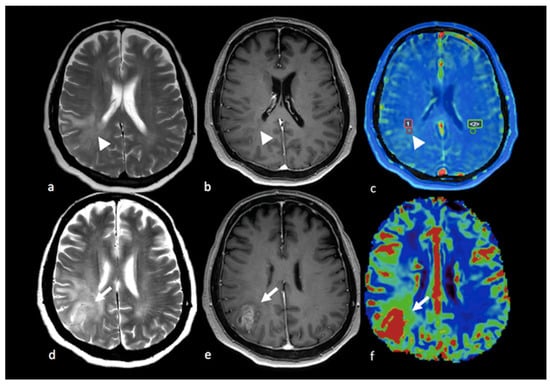

3.2.2. Diffusion Tensor Imaging (DTI)

- Lee, E.J.; Ahn, K.J.; Lee, E.K.; Lee, Y.S.; Kim, D.B. Potential role of advanced MRI techniques for the peritumoural region in differentiating glioblastoma multiforme and solitary metastatic lesions. Clin. Radiol. 2013, 68, e689–e697. [Google Scholar] [CrossRef]

- Byrnes, T.J.; Barrick, T.R.; Bell, B.A.; Clark, C.A. Diffusion tensor imaging discriminates between glioblastoma and cerebral metastases in vivo. NMR Biomed. 2011, 24, 54–60. [Google Scholar] [CrossRef] [PubMed]

- Sternberg, E.J.; Lipton, M.L.; Burns, J. Utility of diffusion tensor imaging in evaluation of the peritumoral region in patients with primary and metastatic brain tumors. AJNR Am. J. Neuroradiol. 2014, 35, 439–444. [Google Scholar] [CrossRef]